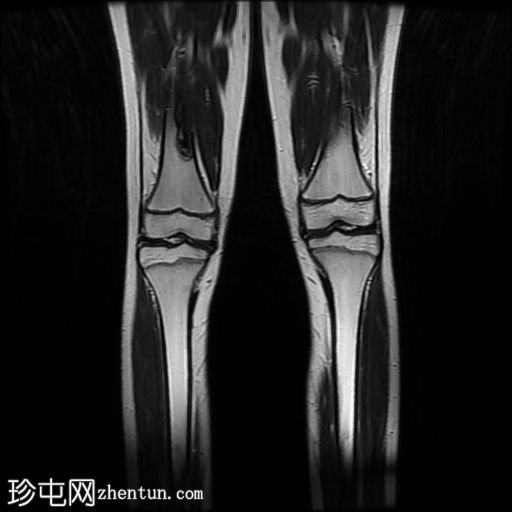

MRI

冠状面

冠状面T1

脂肪饱和度

股骨远端和腓骨近端干骨干部边界清晰的皮质性病变在T1加权图像上主要表现为低信号强度,在T2加权图像上表现为中等/混合信号强度,周边强化较小。胫骨结节骨髓水肿(STIR 和 T1FS/T1+C FS 可见),且无明显软组织肿胀/水肿或远端髌腱增厚/水肿,提示胫骨结节骨骺炎。

患儿出现膝关节疼痛,影像学检查显示胫骨结节骨骺炎。股骨远端和腓骨近端干骺端偶然发现多发性皮质性溶骨性病变,提示多发性皮质缺损或非骨化性纤维瘤。这些病变通常无症状,在影像学检查中偶然发现。